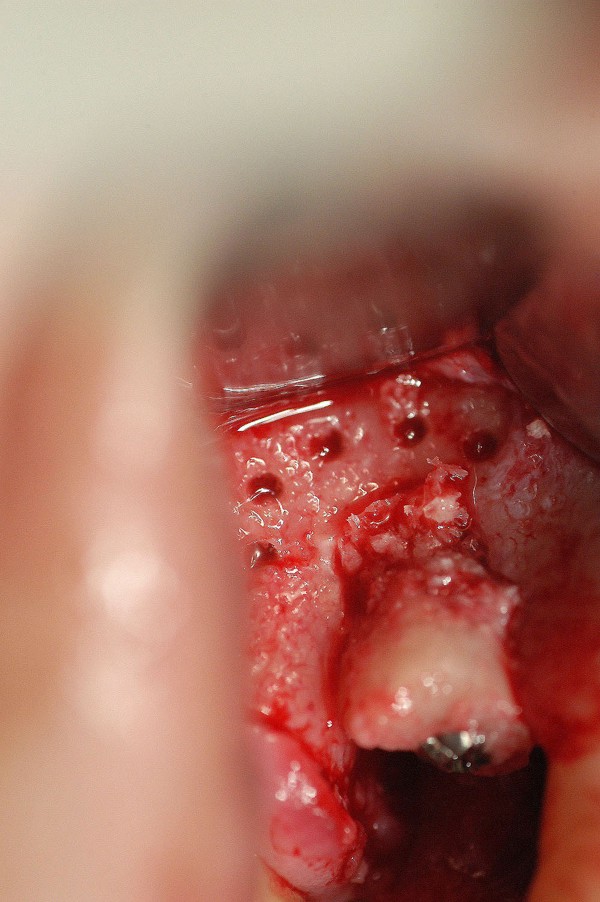

EFECTOS DEL TABAQUISMO CRÓNICO SOBRE LA IRRIGACIÓN ÓSEA TERMINAL. Es por todos conocido el efecto deletéreo que el uso del tabaco provoca sobre la irrigación terminal de mucosas y hueso. Su uso además produce un aumento en la frecuencia cardíaca y la presión arterial, volumen sistólico y gasto cardíaco, a sí como del flujo sanguíneo coronario. vasoconstricción cutánea con una disminución asociada de la temperatura cutánea, y un aumento del flujo sanguíneo muscular. Muchas veces , la intención terapéutica excede los propósitos del paciente de alejarse del tabaco , y se abordan soluciones que terminan en fracasos. Paciente mujer de 53 años de edad, carente de enfermedades, fumadora de dos paquetes diarios de cigarrillos, bruxómana. Se presenta con dolores en la zona de un premolar superior, que porta corona de porcelana sobre un perno colado de oro, con su correspondiente tratamiento de conducto, realizados en mi consulta, veinte años atrás. Se procede a extraer la pieza dentaria, y se observa la pérdida total de la tabla vestibular. Transcurridos seis(6) meses, tiempo mas que suficiente para la conveniente formación de nuevo hueso, se procede a implantar, observándose entonces, que no solo no existía osteogénesis, sino que además se había reabsorbido también la tabla palatina y parte del hueso periférico al canino. En un intento heroico de resolver el caso, se procede a tomar un injerto autólogo de la zona del trígono retro molar, y fijarlo mediante micro tornillo de síntesis en la zona afectada, realizando perforaciones alrededor del lecho quirúrgico a fin de aumentar la irrigación por estímulo traumático del hueso periférico Se vuelve a cubrir con Bioss y membrana Bio Guide, y se sutura convenientemente. Al cabo de otras dos semanas, se expone la porción caudal del injerto, acusando evidentes signos de falta de irrigación. Se retira del lecho receptor, se curetéa y se deja cicatrizar por segunda intención. El caso se encuentra a la espera de solución protética fija. FIG16

Se realiza entonces una Regeneración Ósea Guiada (R.O.G), mediante Bioss y membrana reabsorvible Bio Guide. (INIBSA).

LA FIG 11 CORRESPONDE A LA «ZONA DADORA» DEL INJERTO QUE FUE TOMADO DE LA ZONA RETROMOLAR.

LA FIG 12 ES EN EL MOMENTO DE LA INSTALACIÓN DE DICHO INJERTO

LA FIG 13 CORRSPONDE A LA FIJACIÓN DEL MISMO MEDIANTE UN MICROTORNILLO DE FIJACIÓN, Y LA 14 AL CUBRIMIENTO DEL TODO MEDIANTE HUESO BOVINO MARCA BIOS.